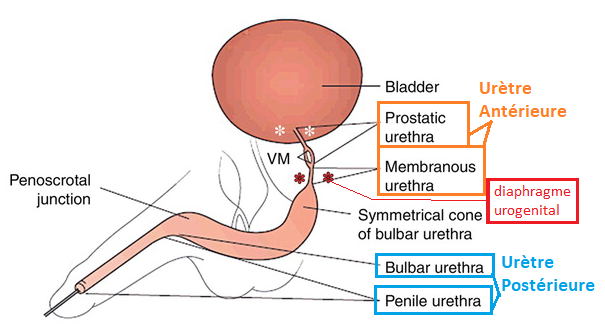

Anatomie